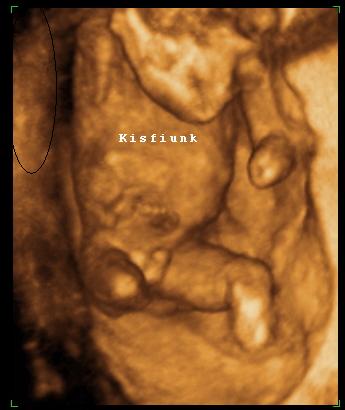

Na és egy kép:

Narancssárga a hasa